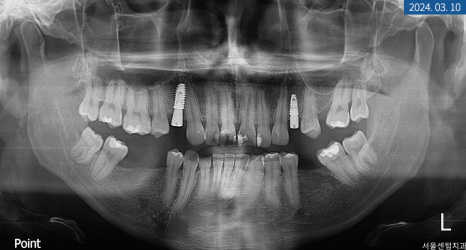

당일 #14번은 잇몸을 열고 GBR 합성골을 이식한 다음 바로 네이바이오텍 픽스처로 고정해 드렸습니다. 환자분이 1차 수술에 진행하길 원하셔서 힐링 어버트먼트로 체결해 드렸죠. 그리고 #24 좌측 소구치는 비절개를 통해 픽스처를 고정한 후 동일하게 힐링 어버트먼트로 체결해 드렸습니다. #14번 소구치는 5개월이라는 골 유착 시간을 가졌으며 #24번은 3개월이 소요되었습니다.

ISQ 장비로 인공 나사와 잇몸뼈가 잘 붙었는지 수치를 체크한 다음 정상 기준에 들어와서 힐링 어버트먼트를 제거하고 코핑을 연결했습니다. 그런 뒤 맞춤 지대주와 크라운 제작을 위해 인상 체득을 하고 다시 힐링 어버트먼트로 연결하게 되었습니다.

2주 후 기공소에서 제작된 커스텀 지대주와 크라운을 수복해 드리면서 마무리했는데요. 치근단 사진을 찍어보니 픽스처 주위에 염증 없이 단단하고 견고하게 고정되었습니다.

두 달 후 재방문을 통해 치근단 사진과 세팔로 사진을 찍어 보니 원하는 위치에 픽스처가 잘 고정돼 있고 주변 구조에 염증 없이 견고하게 자리 잡고 있었습니다. 물론 전체 기간에 환자분이 저작도 마음껏 못하시고 위생 관리에 주의해야 한다는 부분이 있었지만 그래도 수고로운 과정을 견디고 튼튼한 제2의 영구치가 만들어졌습니다.